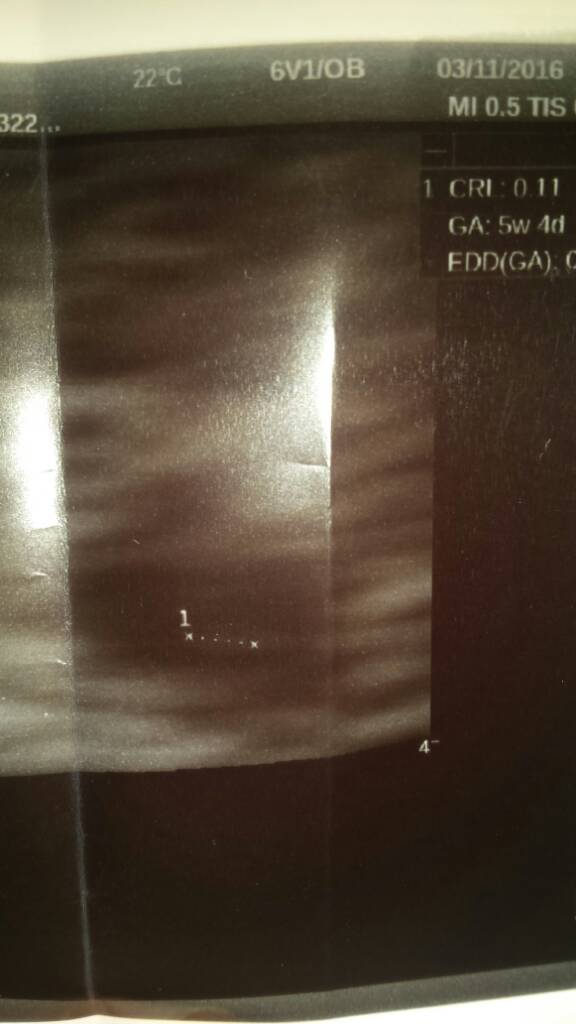

Wczoraj byłam na pierwszej wizycie, ciąża młodsza o kilka dni niż z terminu OM, wg usg wczoraj był 5t5d. Ciąża umiejscowionna dobrze, serduszko bije więc to najważniejsze!  zmartwiło mnie tylko to, że na usg było wydać cechy odklejającej się kosmówki ;( dostałam Luteinę na podtrzymanie i nie mogę już pracować, mam unikać skupisk ludzi by nie zachorować oraz oszczędzać się. Czy któraś z Was miała podobny problem na początku ciąży? Dodam, że w poprzedniej ciąży wszystko było ok...

zmartwiło mnie tylko to, że na usg było wydać cechy odklejającej się kosmówki ;( dostałam Luteinę na podtrzymanie i nie mogę już pracować, mam unikać skupisk ludzi by nie zachorować oraz oszczędzać się. Czy któraś z Was miała podobny problem na początku ciąży? Dodam, że w poprzedniej ciąży wszystko było ok...

Ja mam dokładnie to samo też pierwsze usg 5t5dz, też ciąża o kilka dni młodsza niż z om. Podejrzenie krwiaka lub z uwagi na bardzo wczesną ciążę nie do końca połączona kosmowke z czymś tam [emoji6] Dostałam duphaston na podtrzymanie. Zakaz dźwignia i przemeczania się ale mogę normalnie funkcjonować. Wizyta była 16.11 i od tego czasu odpukać nie mam krwawienie ani innych niepokojących objawówWczoraj byłam na pierwszej wizycie, ciąża młodsza o kilka dni niż z terminu OM, wg usg wczoraj był 5t5d. Ciąża umiejscowionna dobrze, serduszko bije więc to najważniejsze!zmartwiło mnie tylko to, że na usg było wydać cechy odklejającej się kosmówki ;( dostałam Luteinę na podtrzymanie i nie mogę już pracować, mam unikać skupisk ludzi by nie zachorować oraz oszczędzać się. Czy któraś z Was miała podobny problem na początku ciąży? Dodam, że w poprzedniej ciąży wszystko było ok...